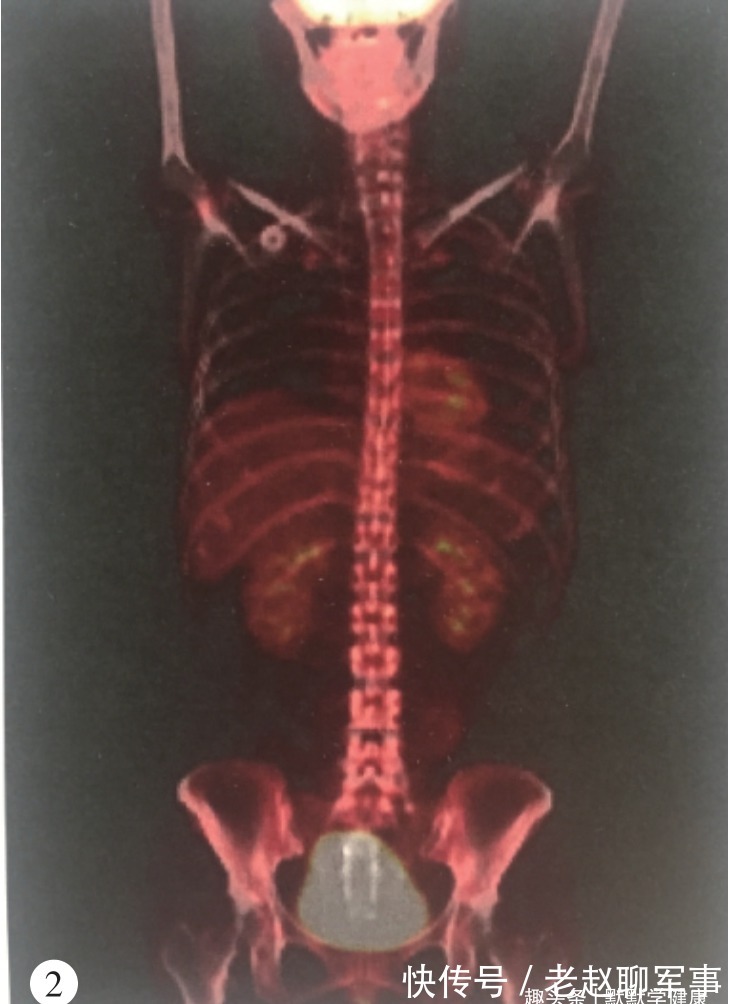

(2014年7月PET-CT结果)

于是,继续按这个方案化疗3个周期,2014年11月开始单药吉西他滨维持治疗4个周期,出现血小板减低及药物性肝损伤,以乐启生培本消癌IV方加减治疗,提升免疫力,消除化疗副作用带来的不适。2015年10月停止化疗,改用口服中药维持。